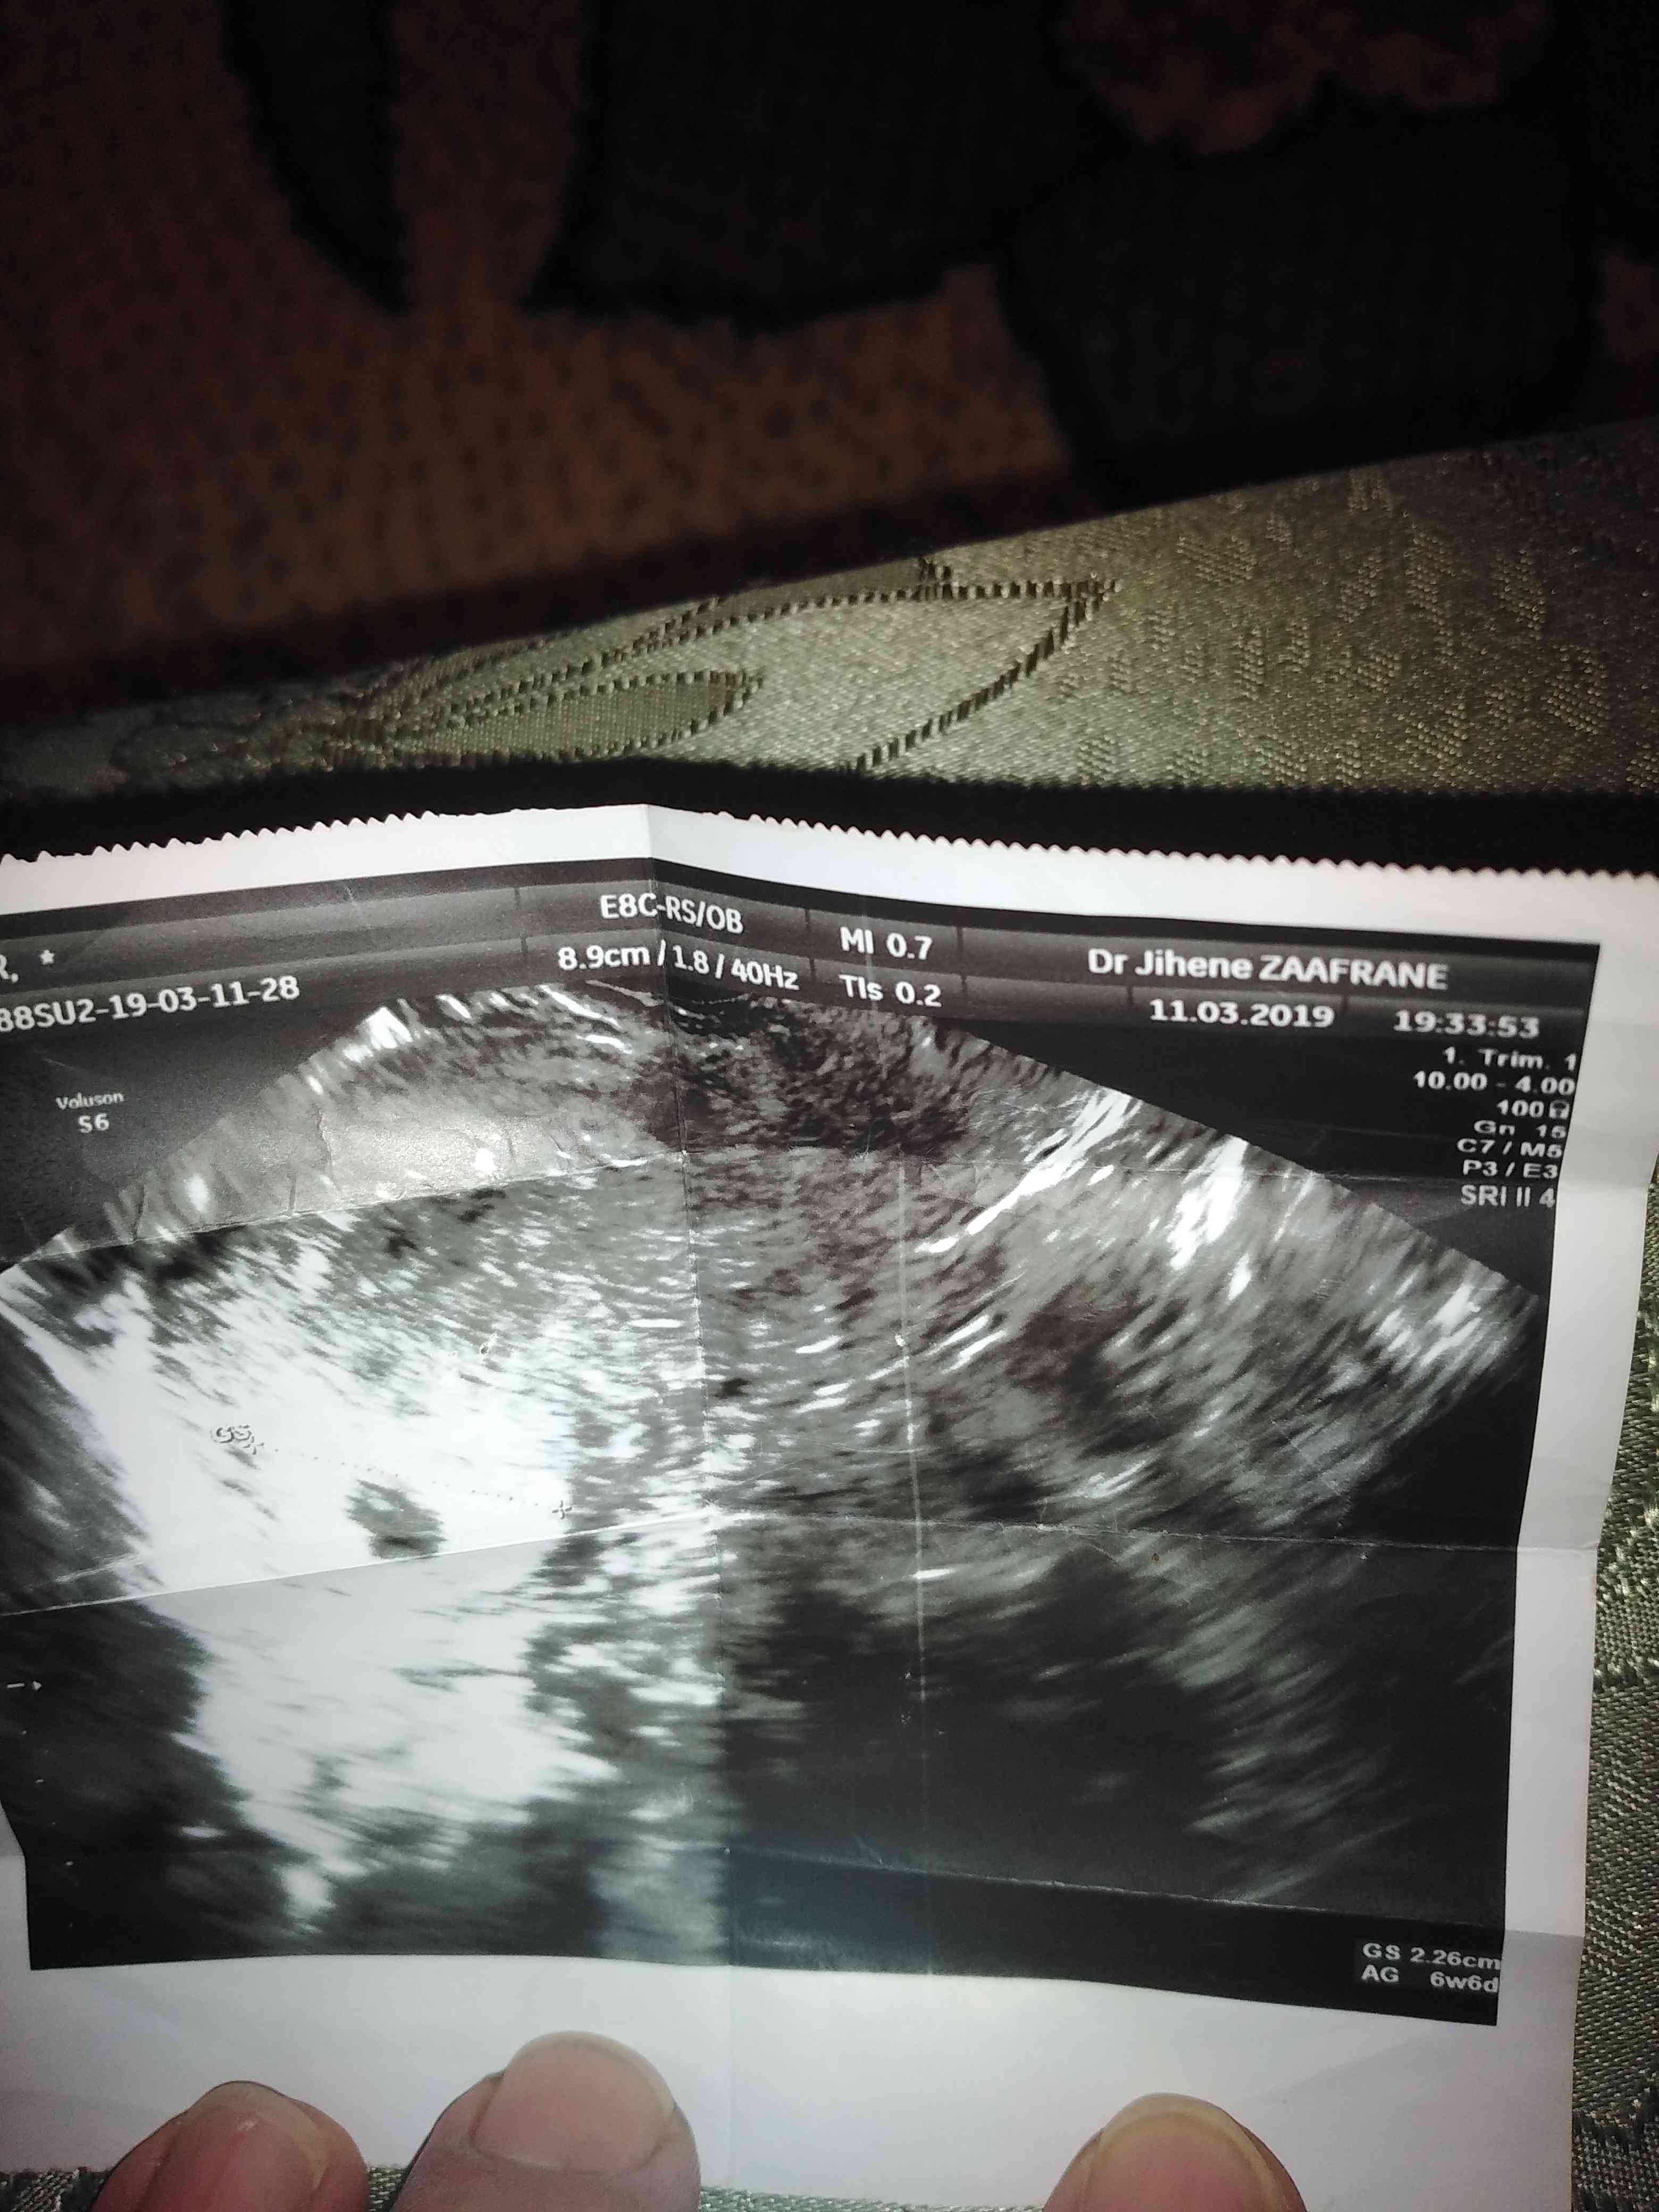

اريد قراءة صورة السونار ومعرفة تفاصيل الرموز

قراءة السونار المهبلي

ممكن قراءة السونار المهبلي من فضلكم

هل يمكن قراءة اشعة السونار المهبلي اريد أن أعرف اذا يوجد حمل او تكيسات او التهابات ظاهرة